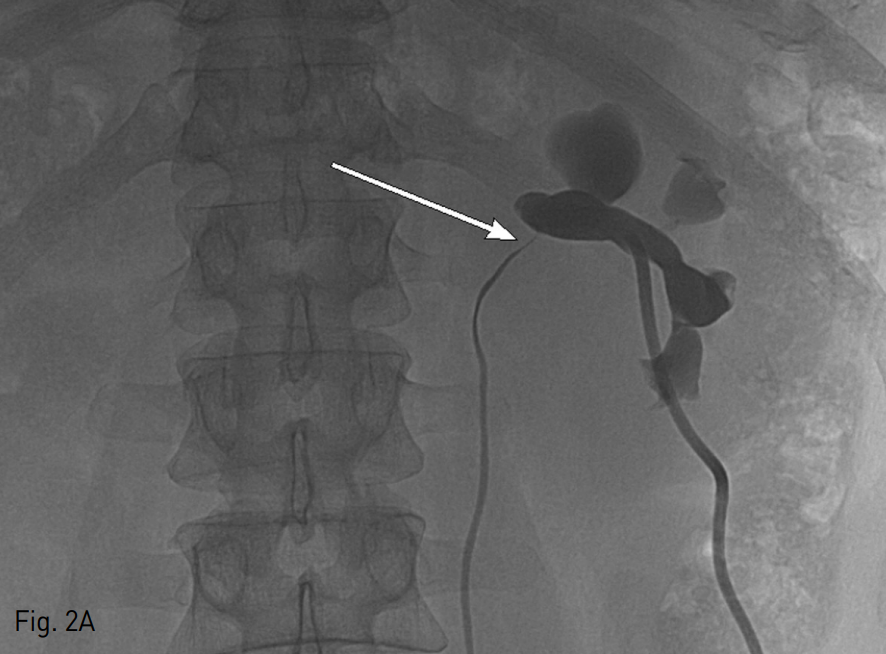

복부 CT상 좌측 신장에 약 5cm 크기의 단순낭종과 수신증이 관찰되었다. 단순낭종에 의한 요관신우연결부위 (ureteropelvic junction)의 협착으로 수신증이 발생된 것으로 생각되었고 좌측 신장에 작은 결석이 있었지만 이로 인한 수신증은 아닌 것으로 보였다 (Fig. 1).

Fig. 1

Abdominal enhanced coronal CT scan shows simple renal cyst in left kidney (arrow) and hydronephrosis (arr owhead).